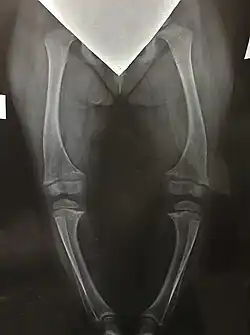

- Прогрессирующая деформация нижних конечностей с момента начала ходьбы (варусная деформация, вальгусная деформация, по типу «дующего ветра»);

- Рентгенография кистей и костей ног для оценки состояния костной ткани (в зонах метафизов трубчатых костей видны характерные для рахита изменения такие, как неровность края метафиза, вогнутость метафиза с истиранием краев кости, формирование бокаловидных вдавлений, повышение прозрачности зоны метафиза);

Нарушение минерализации костей при Х-ГФР приводит к развитию прогрессирующих деформаций ног у ребёнка. Движения ребёнка становятся тяжелыми и ограниченными, происходит развитие артрозов крупных суставов и деформаций позвоночника. Кроме того, деформации ног ведут к выраженному косметическому дефекту, что может являться причиной для серьёзных переживаний ребёнка по поводу своей внешности.

Возможные типы деформаций ног при Х-ГФР

- О-образная (варусная деформация);

- Х-образная (вальгусная деформация);

- Сочетание Х и О-образной (деформация по типу «дующего ветра»).

При выраженных деформациях нижних конечностей с разрушением структуры тазобедренных и коленных суставов, а также при значительном ограничении активных передвижений показано оперативное лечение. Для этого применяются различные хирургические методики.